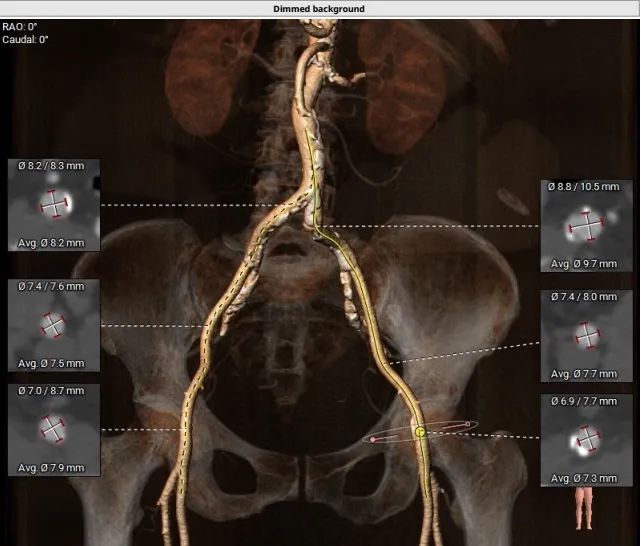

入路情况:

主动脉弓部走行较平缓,可见少许钙化斑块,主动脉弓部三根毛开口未见明显狭窄征象、未见发育变异,胸主动脉、腹主动脉走行稍迂曲,可见少许钙化斑块,管腔未见明显狭窄,双侧髂动脉-股动脉走形稍迂曲,可见钙化斑块,管腔未见明显狭 窄,综合考虑,推荐右侧股动脉做为主入路。右侧股动脉穿刺水平管腔直径约为7.9mm,右侧股动脉分叉约在股骨头中下1/3水平。